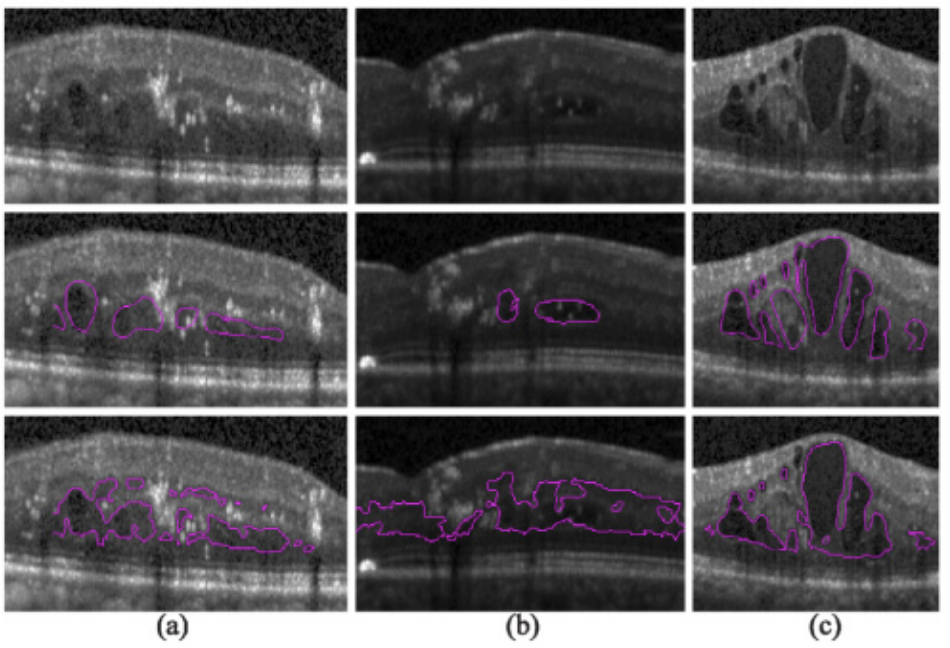

糖尿病性黄斑水肿的OCT图像数据集

数据集下载地址:http://m6z.cn/6xn7cp

使用杜克企业数据统一内容浏览器搜索引擎追溯识别杜克眼科中心医学视网膜实践中的患者,并使用与他们就诊相关的 DME (ICD-9 362.07) 计费代码。然后,一名眼科医生使用标准 Spectralis(Heidelberg Engineering,Heidelberg,Germany)61 线体积扫描协议确定了 6 名临床成像的患者,这些患者具有严重的 DME 病理学和不同的图像质量。